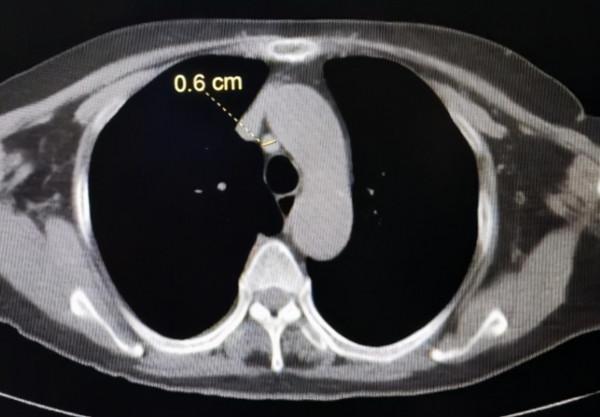

肺微小結節(這裡指<5mm結節)

肺小結節近年來越來越受到臨床醫生重視,因為很多小結節其實是早期肺癌。

但是,隨著科技的提高,CT掃描已經能夠發現1mm左右的結節,再加上這兩年人工智慧的應用,使得肺小結節在CT報告上的出現率“氾濫成災”。再加上很多人寧可錯殺一千,不可放過一個的心態,導致緊張情緒蔓延。甚至連我周圍的同事都出現過這種情況,問醫生A,說不能確定良惡性,醫生B說可以觀察,醫生C說先不用管,自己家人說要不切了吧,省的鬧心!![笑哭]

其實,在最新的國際肺小結節指南上已經把事情說得很清楚了,總結下來就是,對於5mm左右的小結節,隨訪就可以了(不同長相的小結節具體方法不同,但最嚴重的3個月後再次複查薄層CT就可以了,這裡不包括1cm左右的混合磨玻璃結節或者其他有明顯惡性徵象的結節)。總得來說,是個事兒,需要上心,但離癌症還有不小的距離。